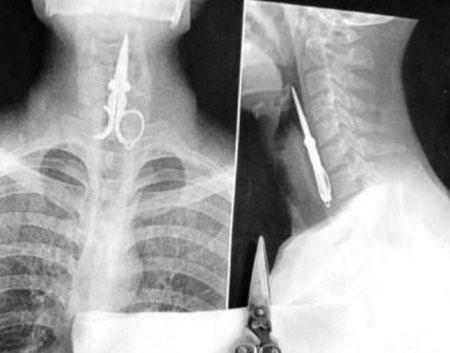

Şoke eden röntgen filmleri

Bu röntgen filmleri görenleri şaşkına çeviriyor!